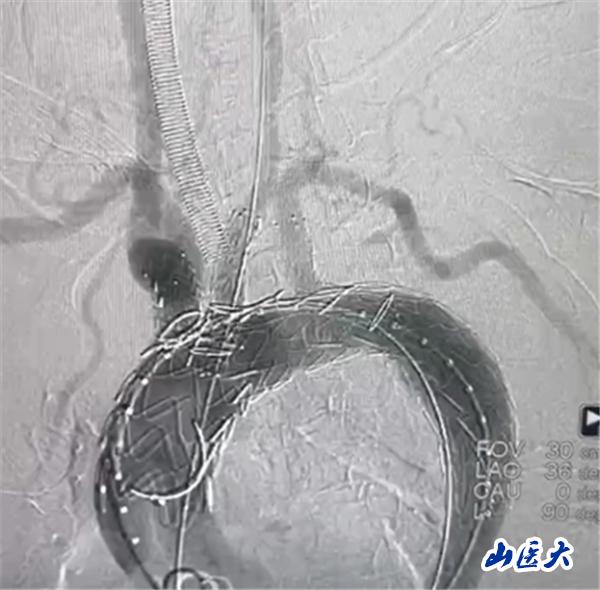

首例患者是一位55岁的女性,她患有高血压约2年时间,平时也会规律服用多种降压药,但血压控制始终不尽人意。2023年4月下午,她出现不明原因的头痛,在家拔罐缓解少许便未到医院就医,次日凌晨突感胸闷、胸背疼痛伴有呼吸困难等症状、家人急忙拨打了120,把患者送入医院急诊科进行救治,医生在急诊科行胸腹主动脉CTA时,显示主动脉弓部-降主动脉及腹主动脉壁间血肿,遂收治入医院血管外科,患者入院10天后复查血肿仍未有改善,依然伴有胸背部疼痛等不适,如不进一步处理,可能发展为夹层危及生命,患者及家属经过与医生团队了解沟通,决定进行创伤小、恢复快的介入手术治疗。张玮教授、符伟国教授、董红霖教授及其血管外科团队(闫盛、常文凯、田琴琴)共同商讨手术方案,最终确定使用Zipper™一体式主动脉弓覆膜支架系统,行胸主动脉覆膜支架腔内隔绝术+无名动脉、左颈总动脉、左锁骨下动脉分支重建术为患者进行治疗。董红霖教授及其血管外科团队根据患者术前头颅CT平扫提示双侧侧脑室旁缺血灶,血压控制不稳定,属夹层壁间血肿非典型夹层等风险点,制定了完整的手术方案,术中经股动脉置入Zipper支架主体,经预留导丝超选无名动脉,并确保主体支架对位准确,顺利置入左颈总动脉、左锁骨下动脉支架,重建弓上三分支。手术过程非常顺利。术后观察主动脉及分支覆膜支架定位准确;无内漏;分支支架通畅,动脉供血正常。

术中造影结果

术后效果